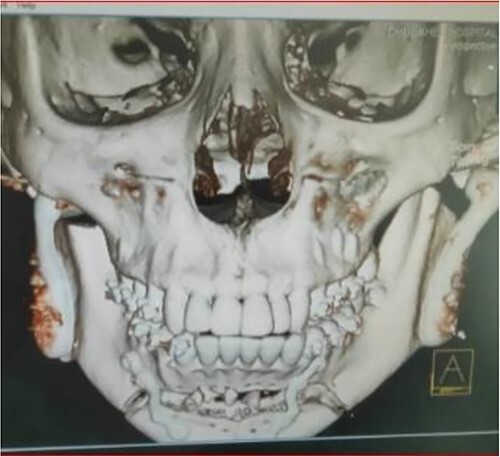

Figure 9.

Postoperative 3D reconstruction of the temporomandibular joint prosthesis with horizontal advancement genioplasty.